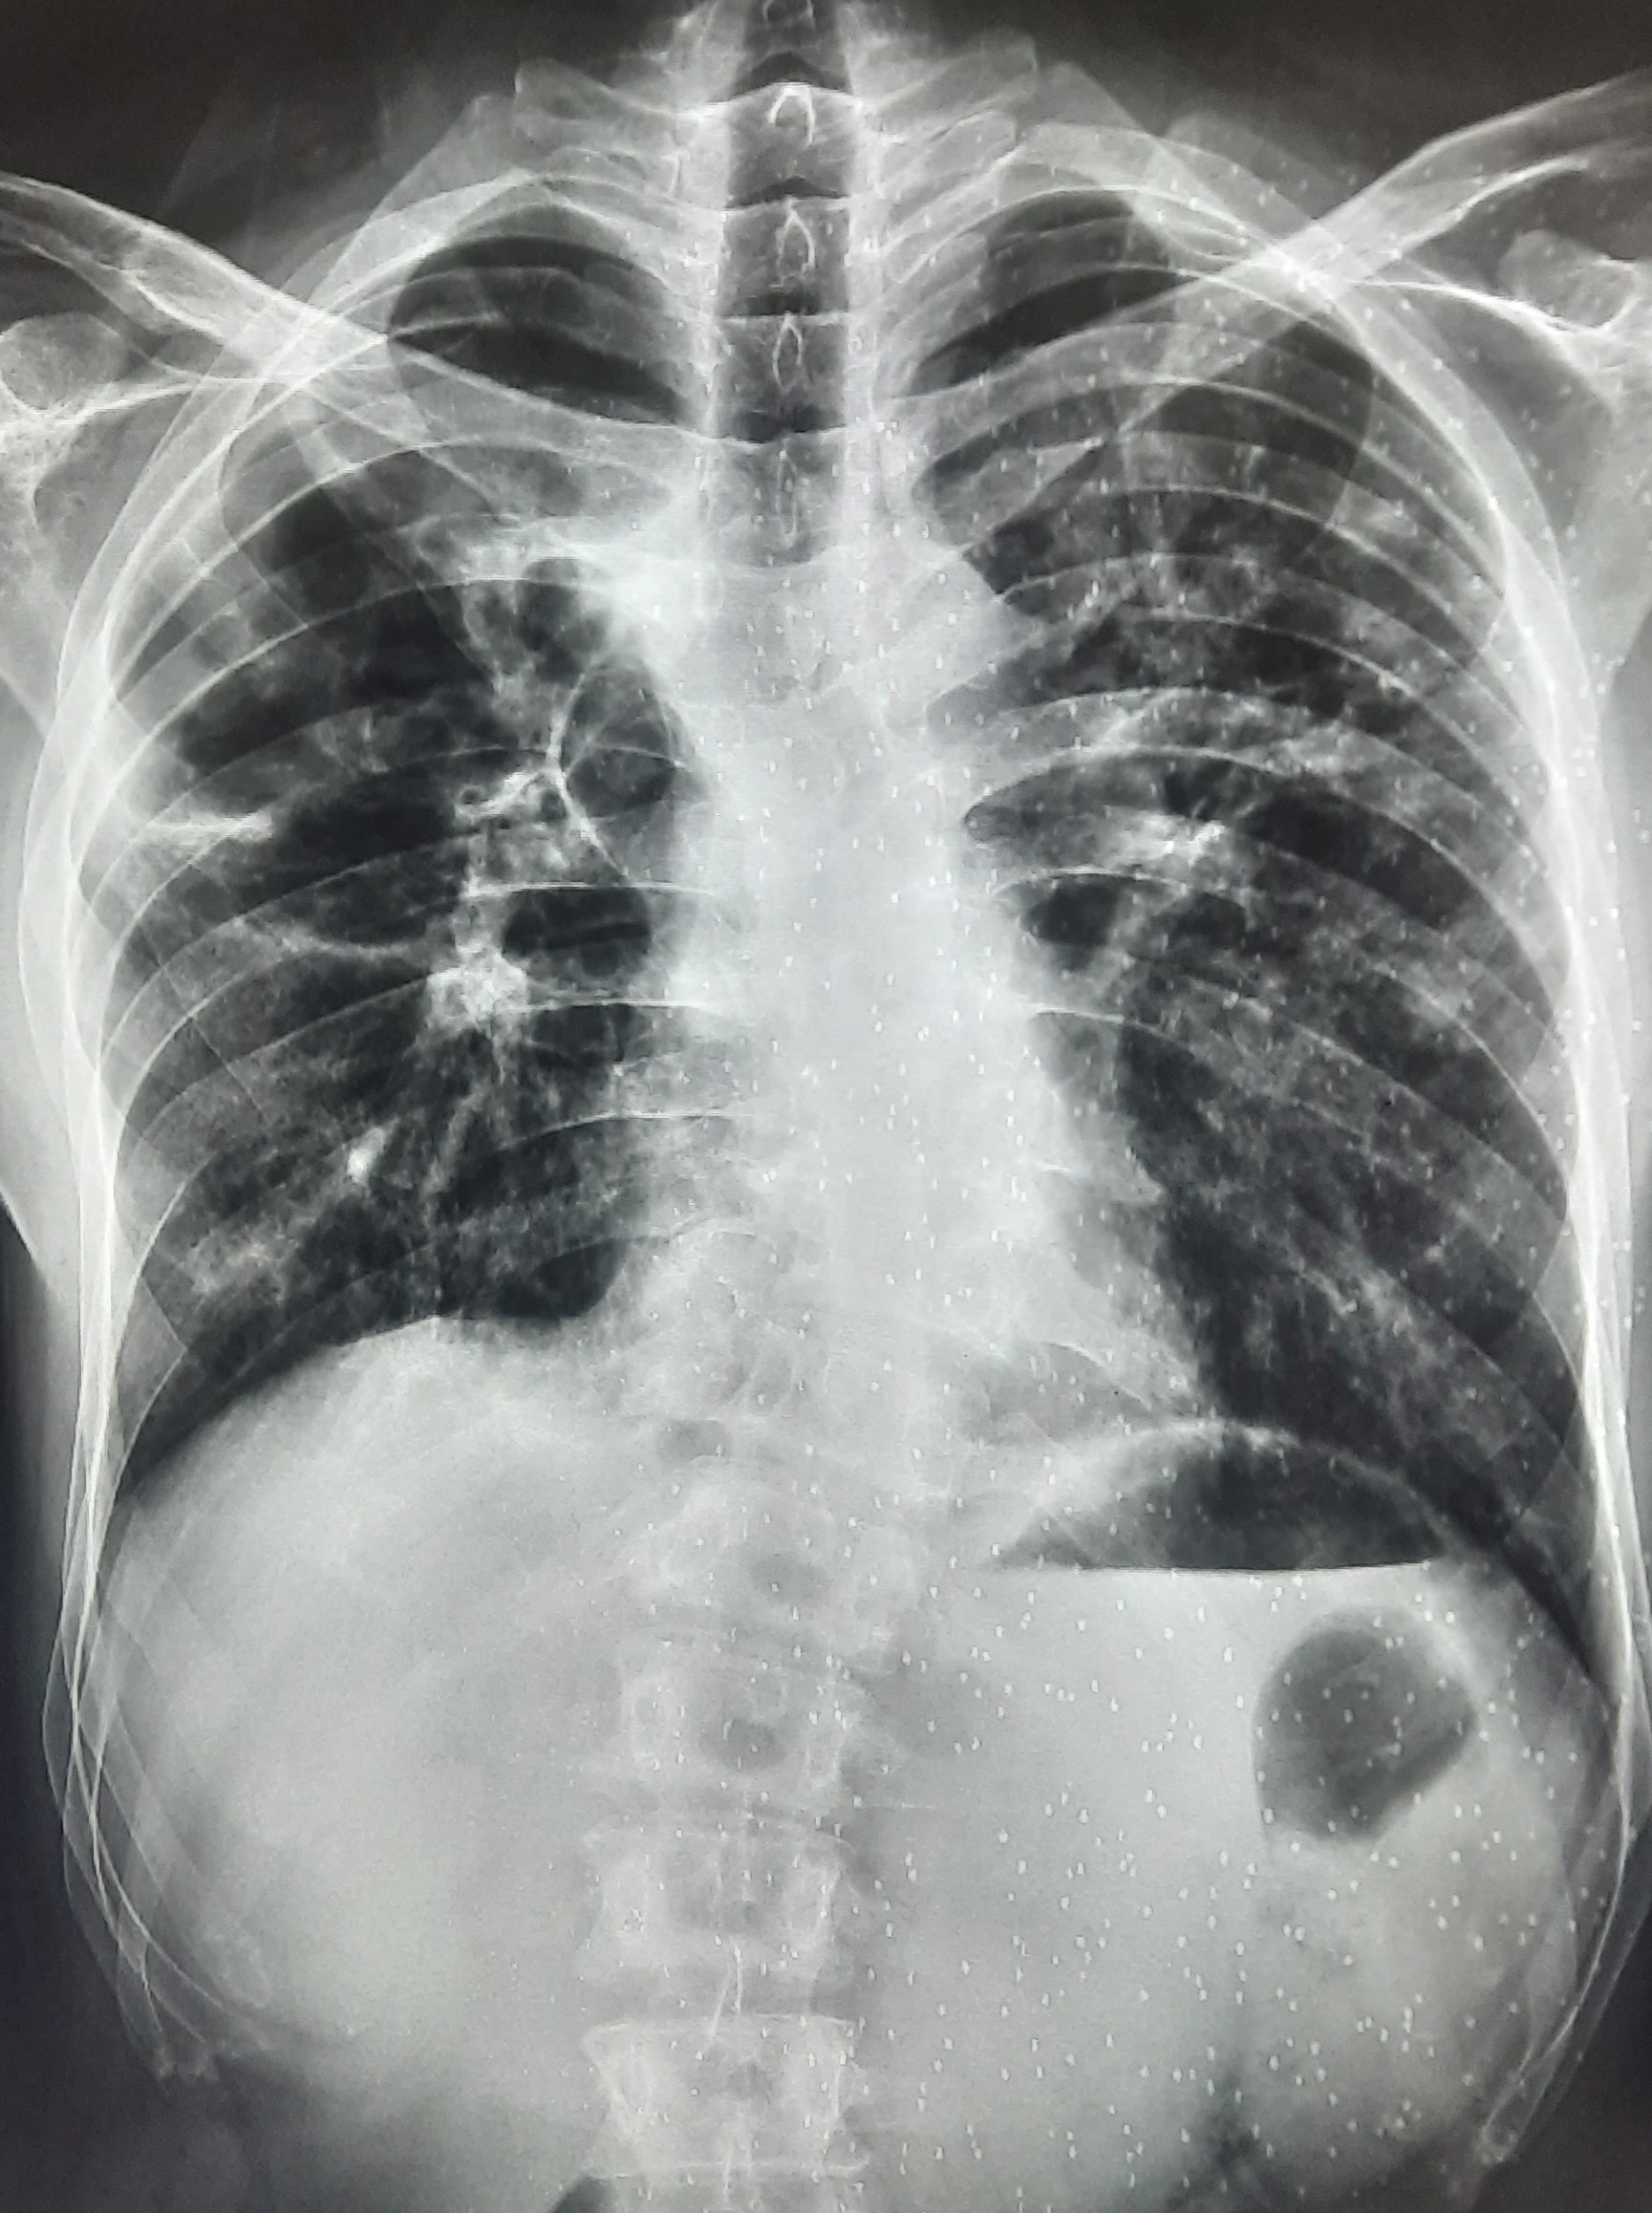

| 283 | IGGMC, Nagpur, Nagpur | P2 | 29-4189 Follow-up of 29-3923 |

Monali Pralhad Milmile | Consent taken on Paper | 46 Yrs. |

Provisional Diag : PTB Follow-up

Final Diag : Pleural Effusion |

TB Case (Confirmed) | Right Sided Upper Zone Fibrotic Lesion, Tracheal Pull Left side, Right sided & Left Sided Pleural Thickening Present, Right sided & Left Sided CP Angle Blunting Present, | Abnormality visible on x-ray |